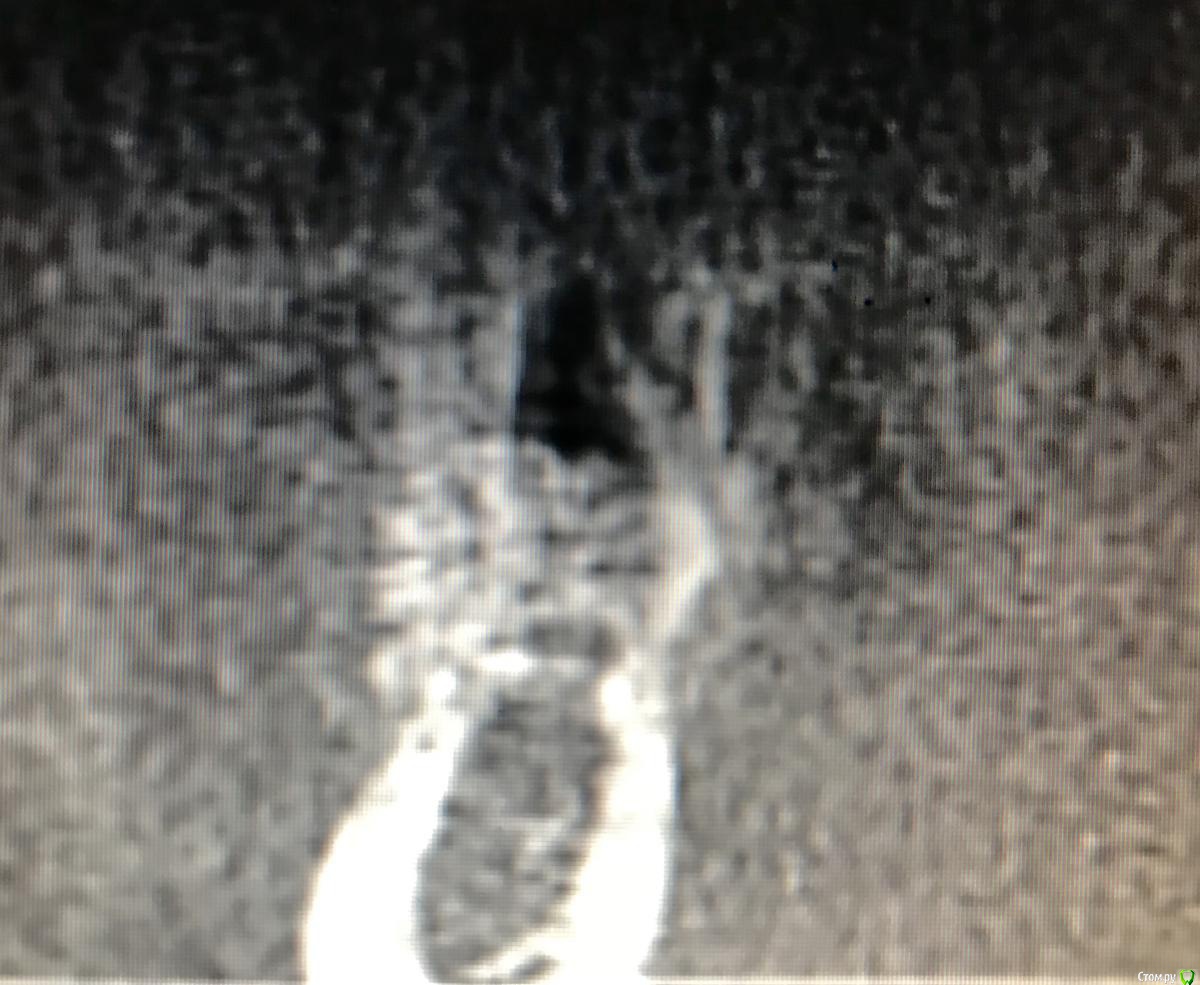

колесников Опубликовано 13 марта, 2019 Автор Поделиться Опубликовано 13 марта, 2019 Ну чтож, прошло 3 месяца,самое время посмотреть что там на кт. 1 Ссылка на комментарий

kladoffka Опубликовано 14 марта, 2019 Поделиться Опубликовано 14 марта, 2019 Вопрос в том, стало ли это костью? Делал как то сосидж, через 6 месяцев на кт все отлично, а при и раскрытии материал так и лежал поверх кости и поднялся вместе с периостом Ссылка на комментарий

колесников Опубликовано 14 марта, 2019 Автор Поделиться Опубликовано 14 марта, 2019 (изменено) Это аллографт,не ксено. Если он интегрирован -он есть,если не интегрирован,не имеет контакта с нативной костью-он лизируется. Это ксерографт может инкапсулироваться и оставаться рентгеноконтрастным. Изменено 14 марта, 2019 пользователем колесников 1 Ссылка на комментарий